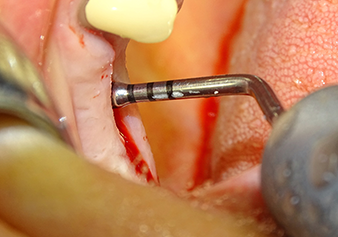

Dopo un controllo intermedio (Fig. 4) è stata eseguita un'ulteriore fase di preparazione (Fig. 5). Lo strumento idraulico Z35P è stato utilizzato in un secondo momento per sollevare la membrana sino alla posizione desiderata (Fig. 6 e 7). In seguito alla suddetta operazione, si è proceduto ad una ulteriore preparazione piezochirurgica della sede dell'impianto conclusasi con l'applicazione della fresa e della fresa a spallamento sul diametro dell'impianto di 4,8 mm. Il materiale di rinforzo (dimensione delle particelle di ca. 0,8 - 1,6 mm) è stato introdotto sotto la membrana di Schneider prima che venisse inserito l'impianto (Fig. 8).